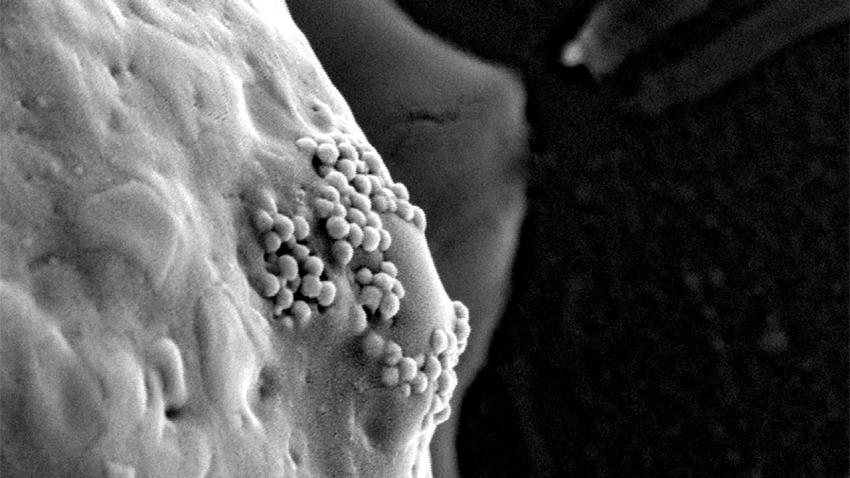

Những cụm hạt vàng dưới kích thước nano đang bị tế bào ung thư nuốt vào bên trong.

Trong quá trình phát triển và bành trướng, các tế bào ung thư sẽ bao bọc và nuốt chửng các hạt nano vàng này vào bên trong. Sau đó, các nhà khoa học sẽ chiếu sáng các hạt nano vàng bằng tia laser hồng ngoại, các hạt này sẽ nóng lên với nhiệt độ cao và tiêu diệt các tế bào ung thư.